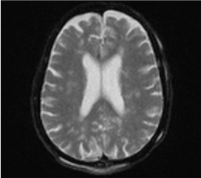

A 75-year-old patient with no pathological history admitted to the emergency room for cranio-facial trauma following a road accident. The admission examination found: a conscious woman with a score of 15 on the Glasgow coma scale (GCS), equal and reactive pupils without sensory-motor deficit or convulsions, eupneic saturated at 100% in ambient air, with a tachycardia at 110 beats/min and blood pressure at 150/90 mmHg, cranio-cerebral computed tomography (CT) revealed a displaced fracture of the ascending branch of the left mandible without brain abnormalities requiring surgical management. 20 hours later the patient presented a consciousness disturbance, the examination revealed a GCS at 9 associated with a right hemiparesis with bilateral thoracic and conjunctival petechiae, fever at 38.5°C. tachycardia at 126 beats/min and blood pressure at 157/95 mmHg, The head CT scan did not show any abnormality, on the other hand the biology shows anemia at 10 g/dl and moderate renal failure (urea at 0.84 g/l and serum creatinine at 14.7 mg/l), the serum electrolytes was without abnormality, the same thing for the coagulation profile. The lumbar puncture made negative. Following the neurological worsening (GCS to 5), the patient was intubated and put on mechanical ventilation, an Angio- MRI was carried out objectifying: areas in hypersignalin T2 and diffuse flair periventricular and oval centers with vascular microangiopathy lesions on the upper level and with absence of intra- and extra-cerebral hemorrhagic lesion (Figure 1) the evolution was marked by non-improvement, the patient died 15 days later.

Figure 1. Axial section in T2 sequence showing periventricular and oval centers hypersignals

In our case the initial and control CT returned without abnormality while the MRI showed areas of hyperintensity in T2 and diffuse periventricular Flair and oval centers with lesions of vascular microangiopathy on the upper level with corticosteroid atrophy under cortical.